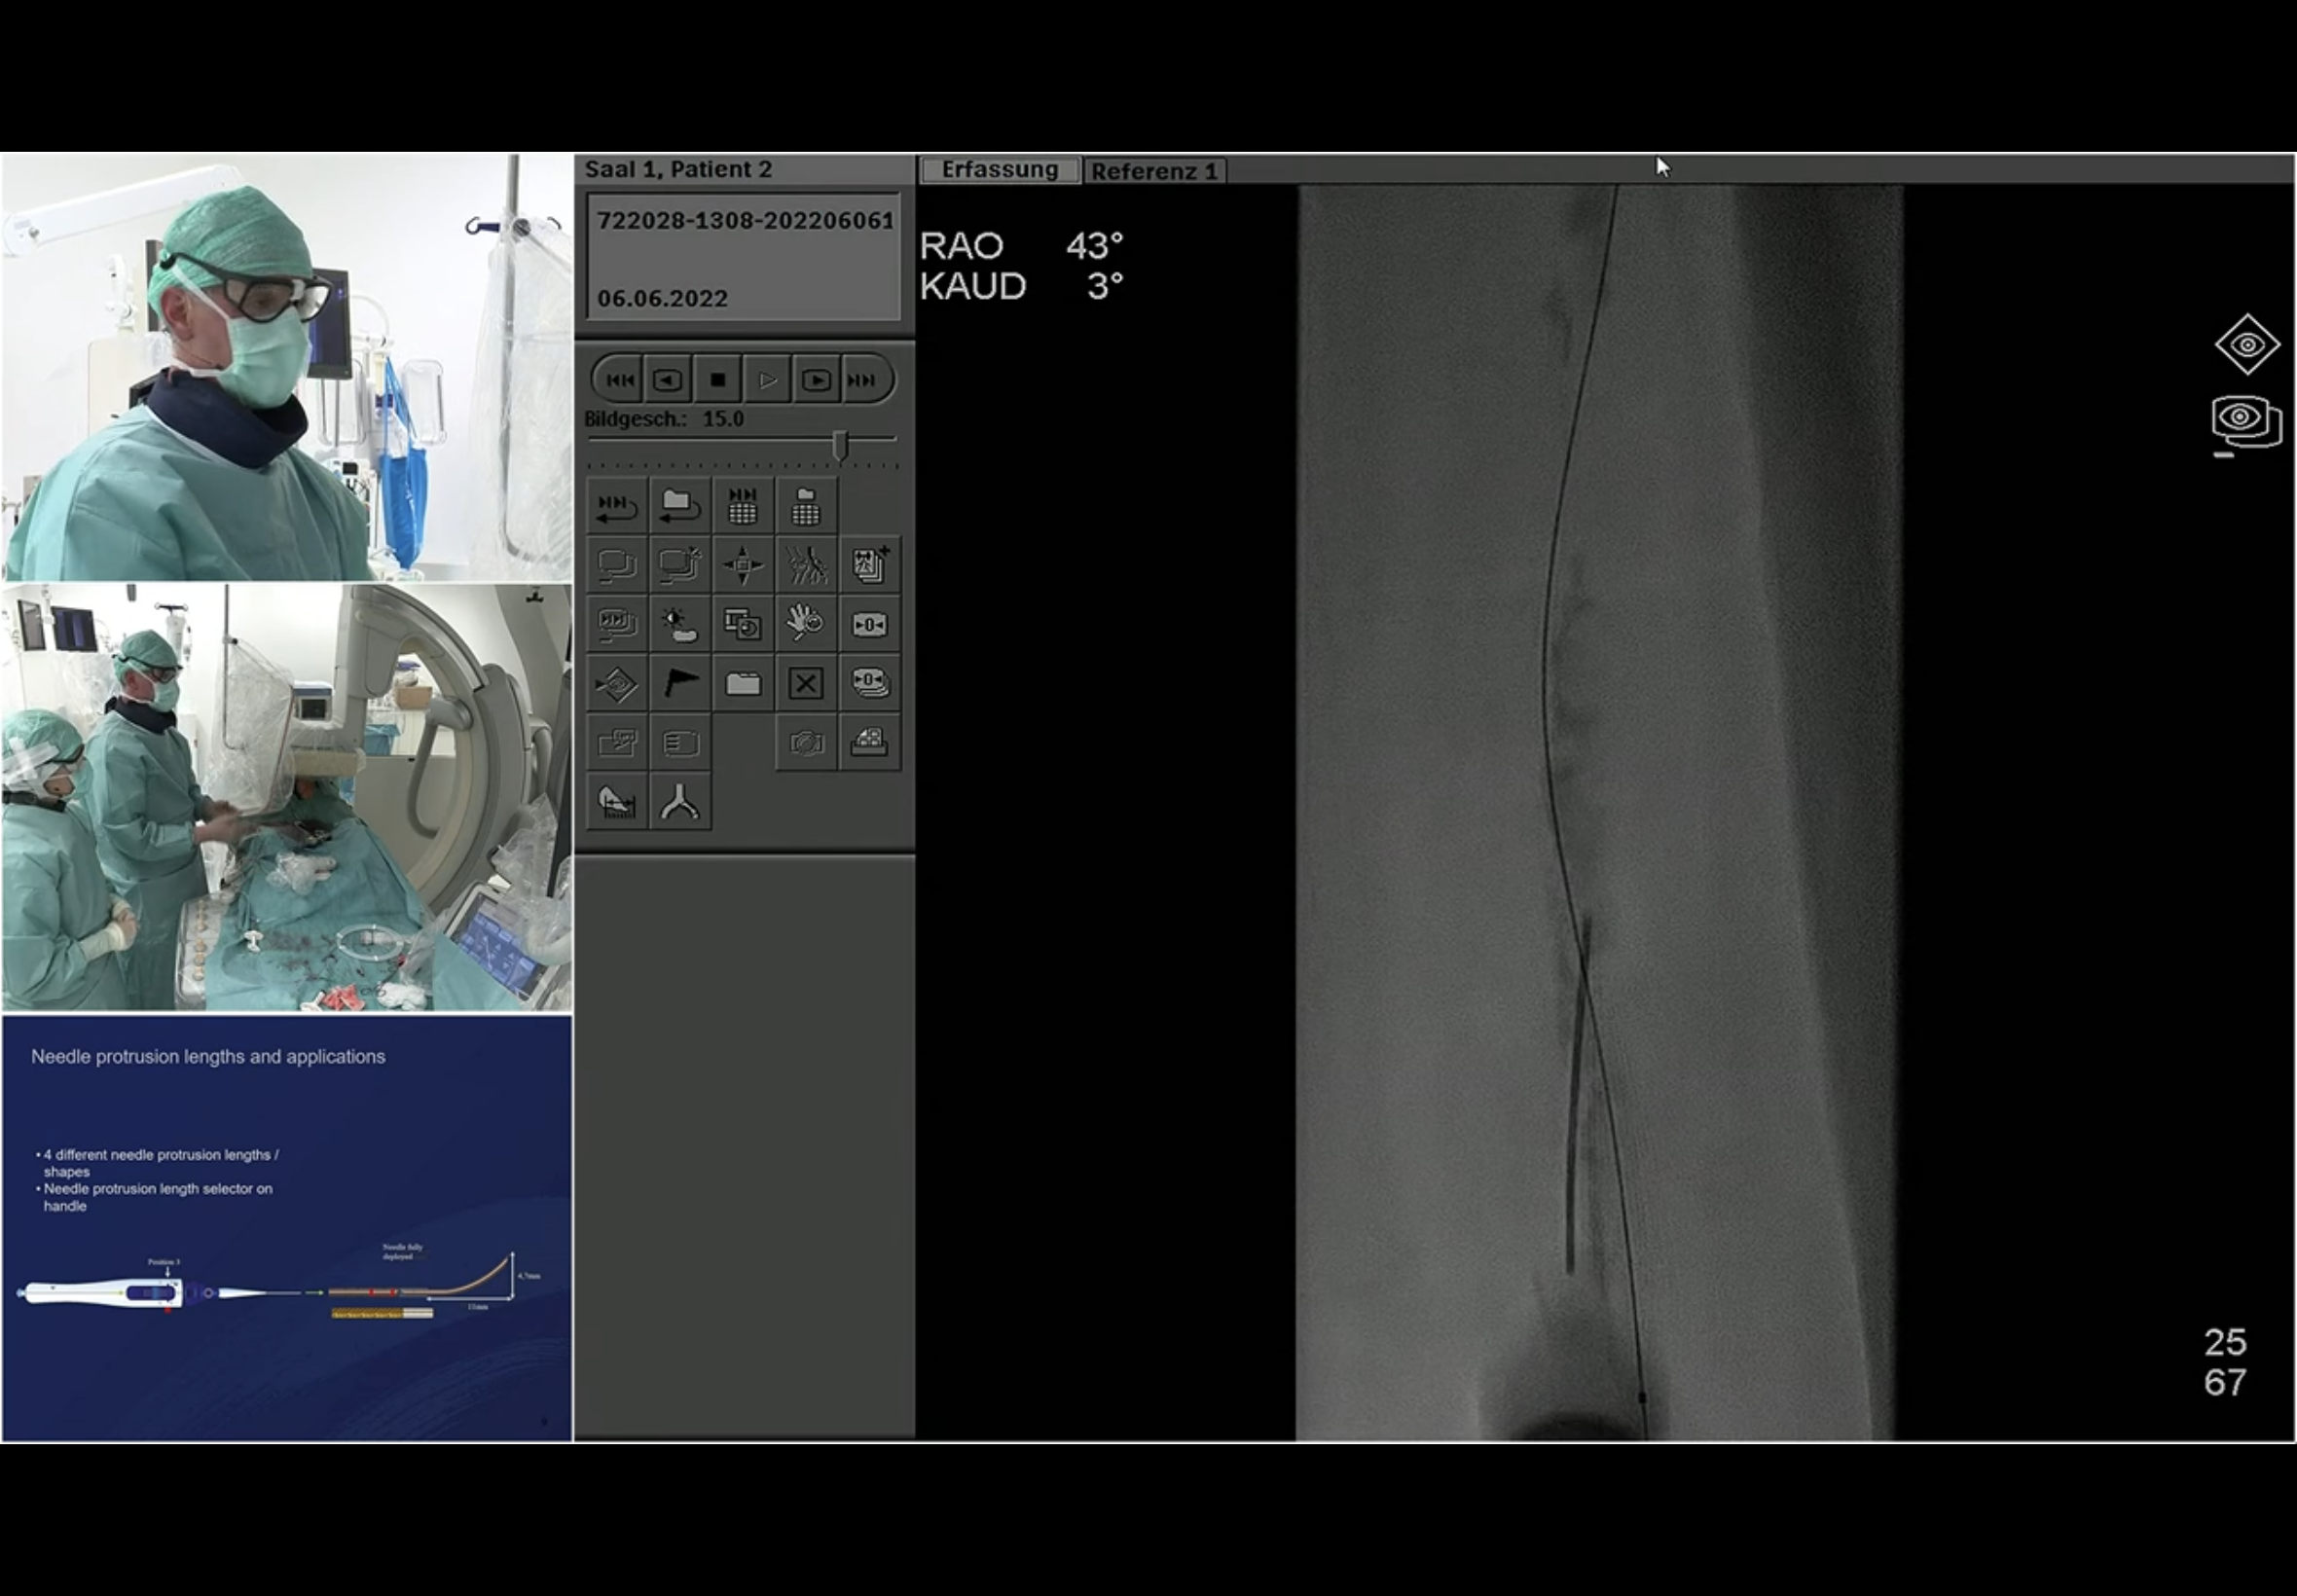

Leipzig Live case Mon 6th Jun 2022 @ 17.25h

Showing the GoBack catheter. Andrej.

Comes in 90 and 120 shaft, it is a 4F catheter.

Too much Calcium, no IL option have to go around the calcium.

Andrej has shoved a lot of LA into the calcium.

Predilated with 3mm balloon.

Then an ultra score 5x200.

used a high pressure 6 x 40 conquest at 40 ATM

Got a bleed in the adductor.

No pain

Using a 7.x 40 balloon

Lots of bleeds

Used a Viabahn therefore - 7 x 150

Orchid 6 x 120 DCB distally

Proxammly also DCB

He will still use a Supera because of the late recoil concern (so will place it INTO the Viabahn)